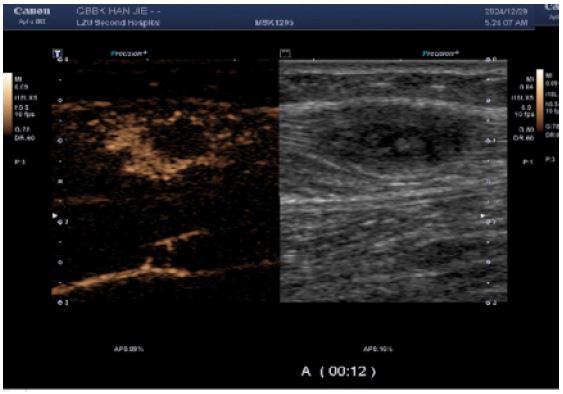

CEUS (performed next day): Demonstrated multiple hypoechoic foci in the left calf muscle layer. At 12 seconds post-contrast injection, lesions exhibited heterogeneous hyper-enhancement (> adjacent muscle tissue) with irregular non-enhancing areas.

Figure 3: CEUS suggested heterogeneous hyper-enhancement at 12 s of contrast injection.

Images are Not Display Check it

Figure 4: The enhancement borders were clear, and areas of non-enhancement were seen within them; Irregular non-enhancing areas are present throughout the enhancement pattern, consistent with a benign enhancement pattern.